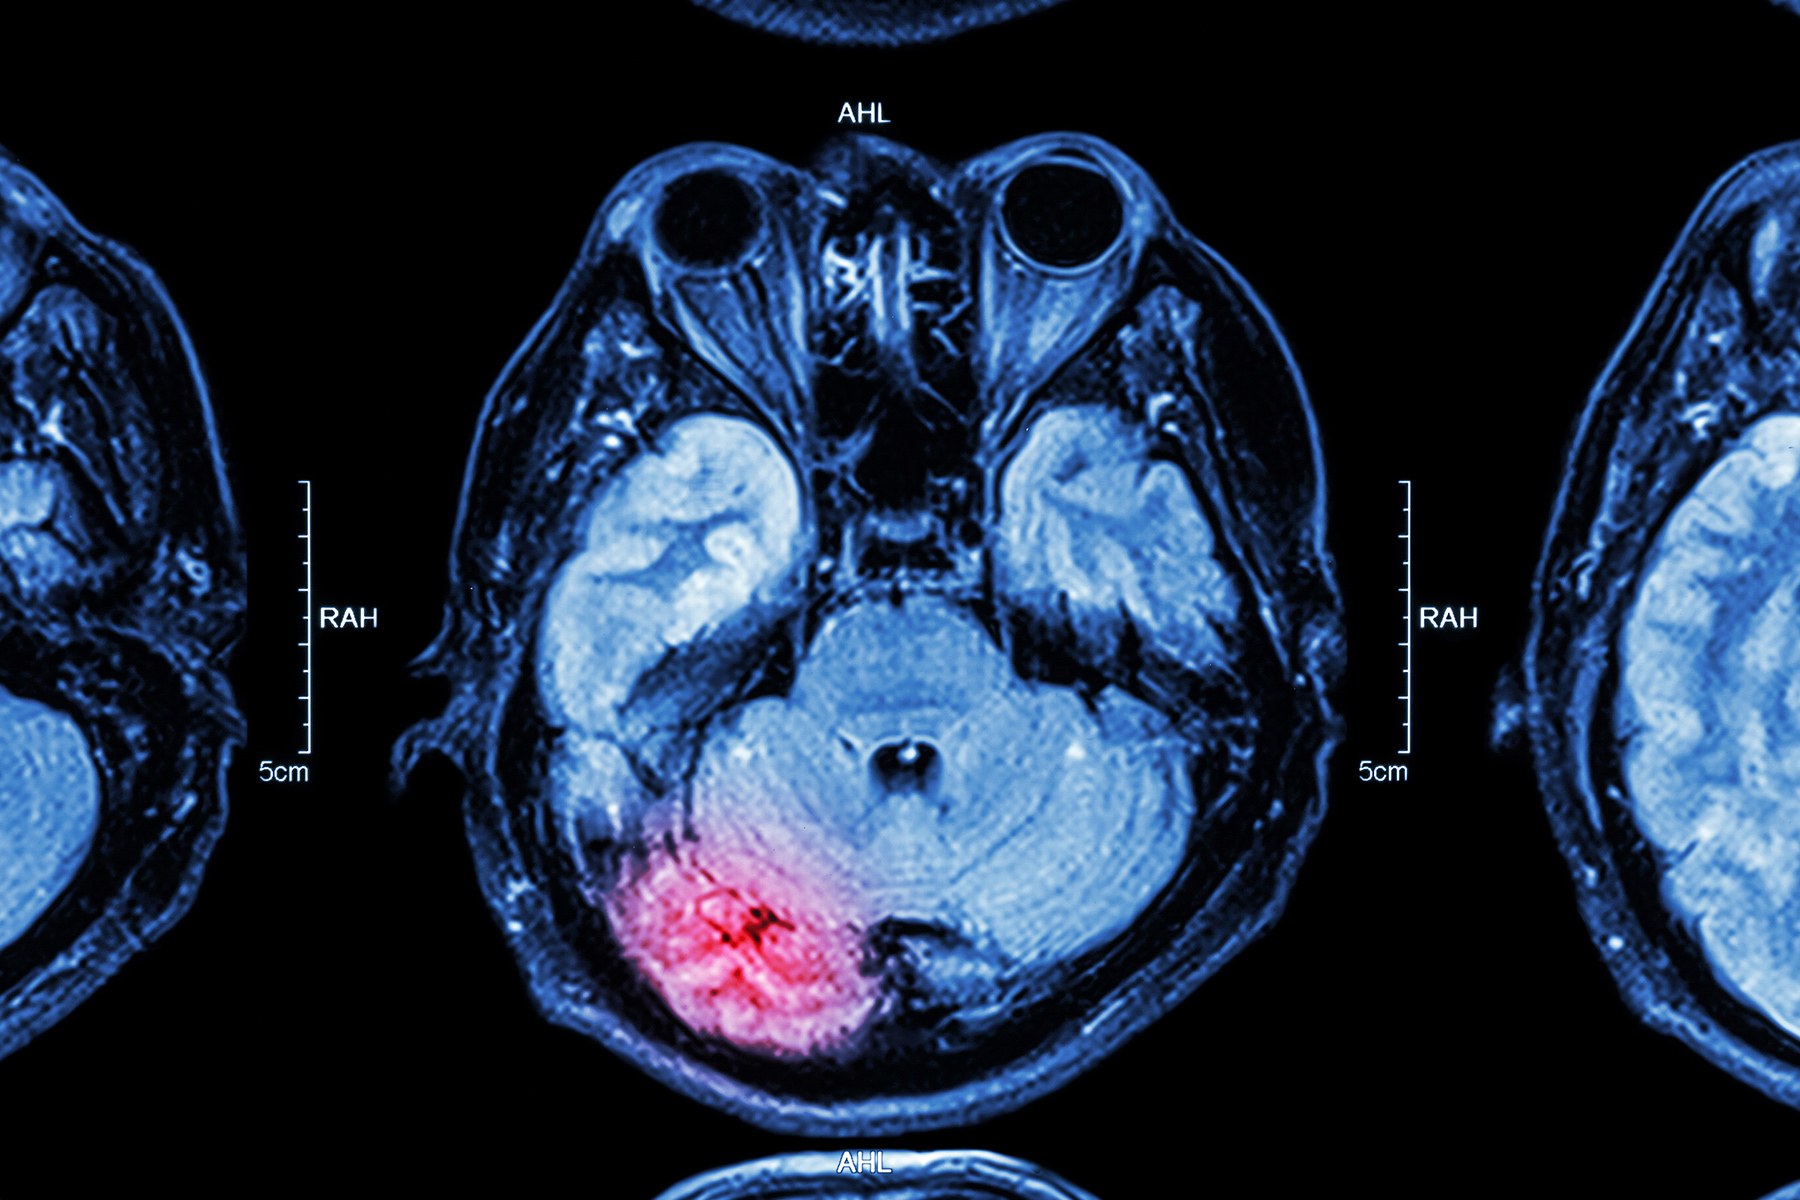

中风

中风有时会损伤控制膀胱的神经。出现尿频或少尿。也可能一次排出大量的尿。帕金森症,多发性硬化症和其他脑部疾病可能具有类似的作用。改变饮食和去洗手间的习惯,可以减轻症状。在严重的情况下,可能需要药物或手术。